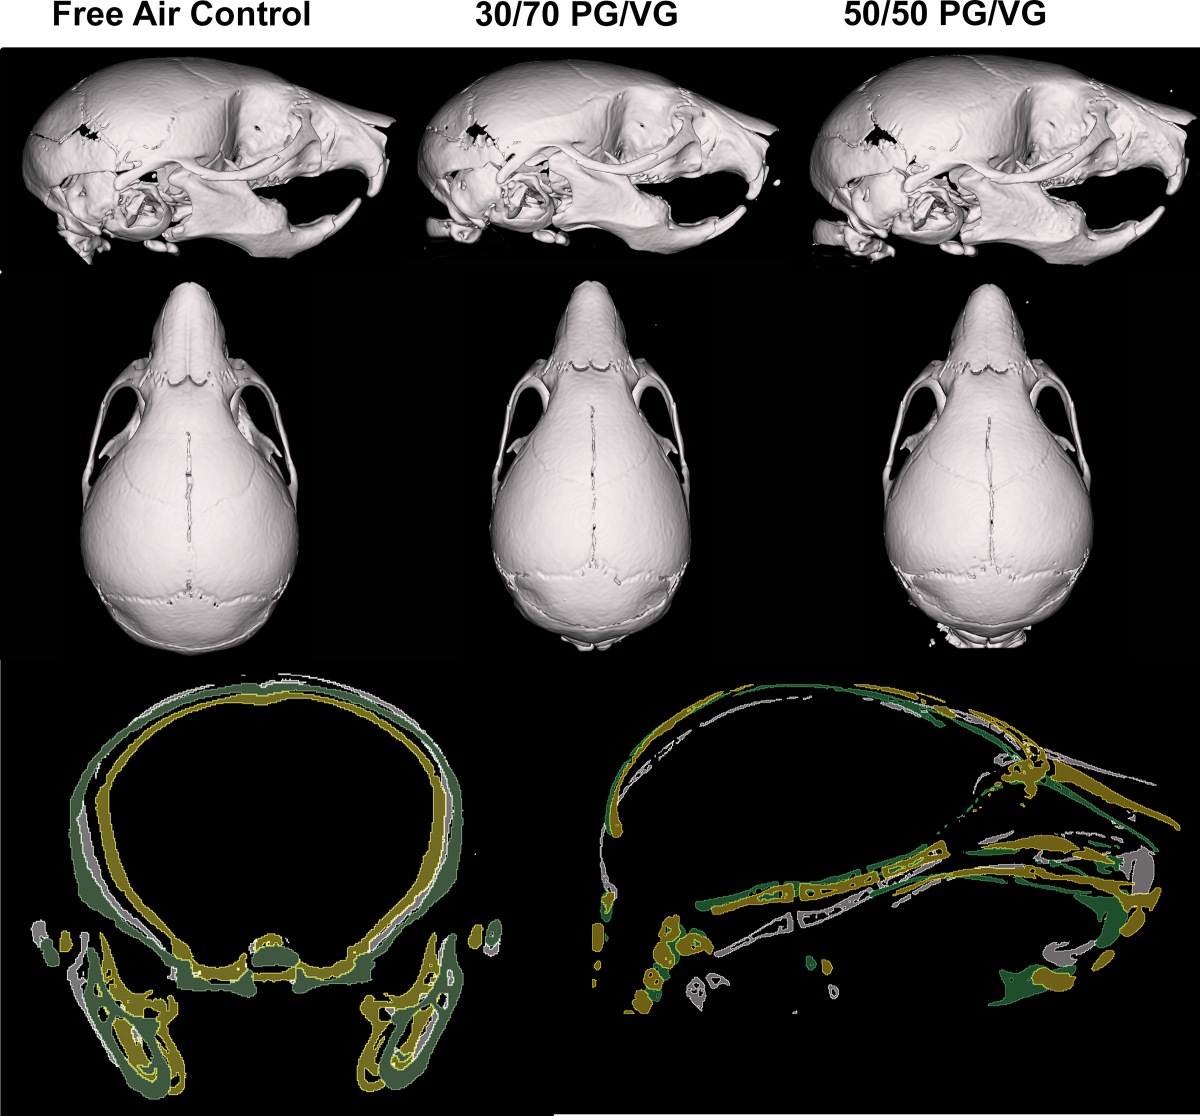

전자담배 액상 성분으로 많이 쓰이는 프로필렌 글리콜(PG)과 글리세롤(VG)의 비율을 각각 3 대 7과 5 대 5로 혼합한 에어로졸에 임신한 쥐가 노출됐을 때 새끼 쥐의 두개골 모양과 크기를 비교한 이미지. 플로스원 캡처

프로필렌 글리콜과 글리세롤 비율이 5 대 5인 에어로졸에 노출된 어미에서 태어난 쥐는 신선한 공기를 마신 대조군과 유의미한 차이를 보이지 않았다.

오히려 글리세롤 비율이 높은 에어로졸에 노출된 어미에서 태어난 쥐는 다른 그룹에 비해 두개골과 얼굴이 너비나 길이 측면에서 상당히 작았고, 코도 짧았다.